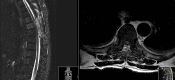

Brown-Séquard syndrome (BSS) is a rare neurological condition caused by a hemi-lesion of the spinal cord and was first described in the 1800s. BSS is characterized by an ipsilateral absence of motor control and discriminatory/proprioceptive/vibratory sensation at and below the spinal level involved, associated with loss of contralateral temperature and pain sensation a couple of vertebral segments below the lesion. BSS is commonly associated with trauma, but can also be iatrogenic. The authors report a case of a patient who presented with neoplastic dorsal spinal cord compression and developed a BSS after surgical decompression and review of the literature of postoperative BSS cases.